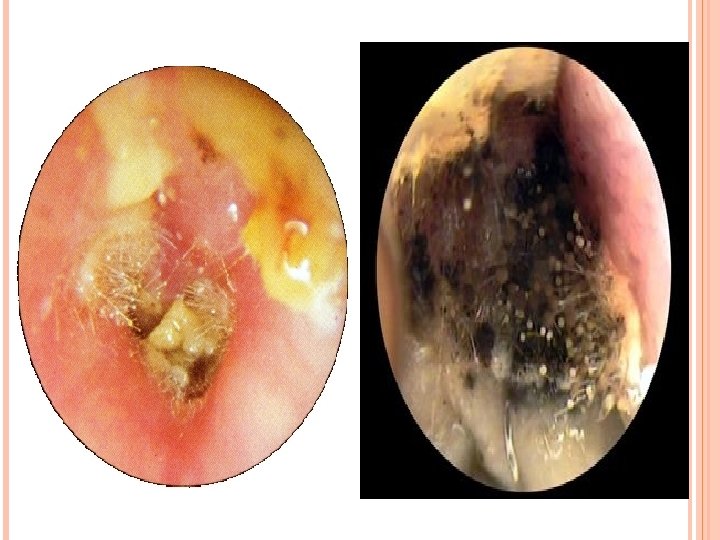

MICOSIS DEL OIDO EXTERNO Las micosis del oído externo son producidas por Candida albicans y Aspergillus niger. Son más frecuentes en inmunosupresivos o inmunodeficientes, diabéticos, alérgicos, estrés, en el verano por la acción del sudor o los baños, que debido a la humedad y al calor favorecen las infecciones por hongos. Se produce una inflamación de la piel del CAE. Los síntomas que produce son picor y otorrea serosa o sero-sanguinolenta en ocasiones. Se diagnostica por otoscopia, se observan formaciones algodonosas blanquecinas en el caso de candida o negruzcas por aspergillus. El tratamiento consiste en la limpieza del CAE y administrar gotas antimicóticas, como miconazol e incluso iodopovidona. Es recomendable no mojarse los oídos mientras dura la infección.